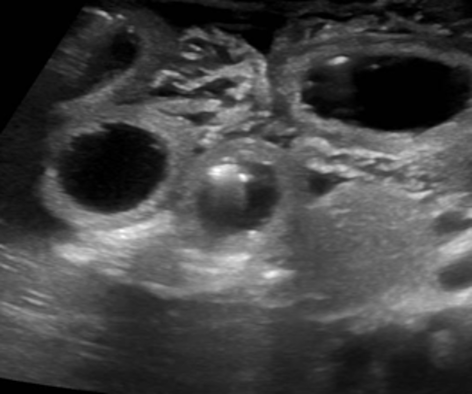

Lecografia addome (Figura 2) eseguita in urgenza, invece, rilevava una marcata distensione di anse del tenue in emiaddome destro, con pareti ispessite e iperemiche, e un marcato ispessimento della radice del mesentere adiacente, che risultava dislocato al fianco destro.

Gli aspetti ecografici e letà del piccolo paziente indirizzavano pertanto la diagnosi verso un volvolo del tenue su probabile malrotazione. Il bimbo veniva pertanto trasferito presso il reparto di Chirurgia Pediatrica, dove veniva sottoposto a intervento di derotazione di matassa intestinale convoluta, resezione di tratto intestinale ileale e anastomosi termino-terminale intestinale.

È pertanto fondamentale includere tra le diagnosi differenziali in lattanti con alterazione dello stato di coscienza, anche patologie addominali acute come il volvolo, che necessitano di una diagnosi tempestiva ai fini di evitare gravi complicanze come la necrosi dellintestino. Lecografia addome si è dimostrata essere un valido strumento diagnostico, di pronta disponibilità, eseguibile al letto del paziente e con un ridotto tempo di esecuzione.